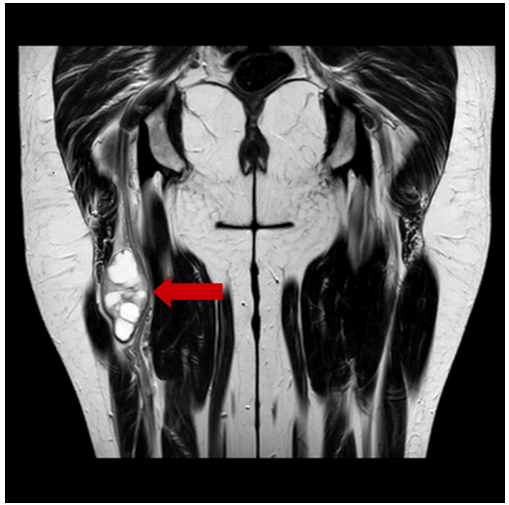

The patient underwent surgery for the exeresis of the tumor. In our case, infragluteal approach was used, pulling away biceps femoris and adductor magnus muscles until the nerve was isolated by plane dissection and neurovascular structures were referenced (Figure 2).

Figure 2 Intraoperative image: nodular tumor with whitish coloration, adjacent to the sciatic nerve in its most cranial portion of the right thigh.

A nodular and whitish-colored tumor was observed next to the sciatic nerve in its most cranial portion of the right thigh. The longitudinal dissection of the peripheral sciatic nerve sheath was performed for complete tumor resection, which was sent to the PA for histological study (Figure 3). The absence of lesion was verified in the proximal and distal ends of the nerve, trying to preserve as many viable nerve fibers as possible.